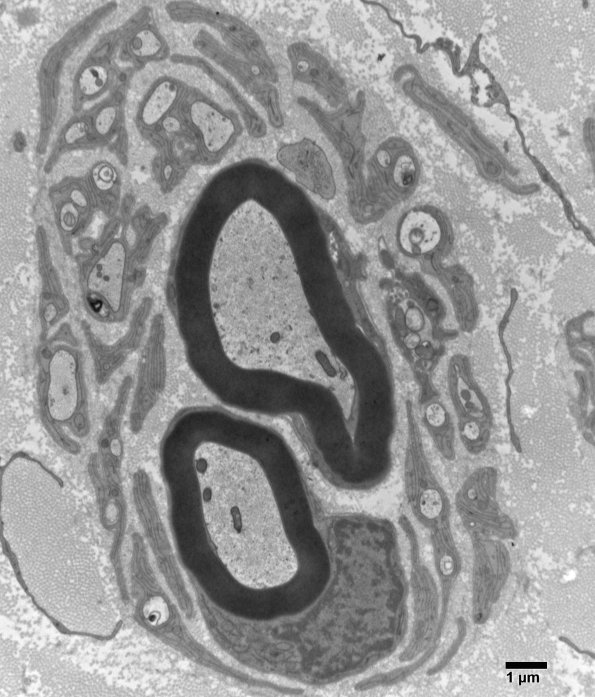

In some cases structures which appear to be onion bulbs by light microscopy appear as marginally associated collections of endoneurial elements. (electron micrographs)